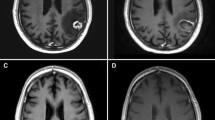

Figure 1 shows the various imaging modalities which can be used to diagnose RN.

a Tumour recurrence: (i) T2-weighted, (ii) post-contrast T1 and (iii) rCBV (relative cerebral blood volume) MR perfusion sequence of a lesion within the left temporal lobe. The lesion quotient of 0.71 and increased rCBV is suggestive of tumour recurrence. b Tumour recurrence: (i) rCBV and (ii) post-contrast T1 showing increased blood flow within the periphery of the lesion, which was histology proven to a tumour recurrence. Radiation necrosis: (iii) rCBV and (iv) post-contrast T1 showing no increase in blood flow. c Mixed picture of radiation necrosis and tumour recurrence: (i, ii) MR spectroscopy and (iii) post contrast T1 showing a growing pericallosal lesion post-WBRT. High lipid-lactate peak seen in radiation necrosis at the right cingulum while increased choline:creatine and choline:N-acetyl-aspartate ratios suggestive of tumour recurrence in the left cingulum. d Tumour recurrence: (i) F-18 FET PET showing amino acid tracer uptake within the enhancing lesion, with (ii) demonstrating the lesion on post-contrast T1 (adapted from Vellayappan B, Tan CL, Yong C, Khor LK, Koh WY, Yeo TT, Detsky J, Lo S, and Sahgal A. Diagnosis and Management of Radiation Necrosis in Patients With Brain Metastases. Front Oncol. 2018 Sep 28;8:395.doi: 10.3389/fonc.2018.00395. PMID: 30324090; PMCID: PMC6172328)